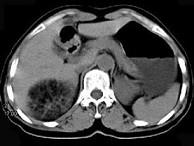

问题 女,53岁,右侧轻度腰背酸痛,行CT检查,如图所示,可能的诊断为()

选项 A.右肾上腺髓样脂肪瘤 B.右肾上腺腺瘤 C.右肾上腺嗜铬细胞瘤 D.右腹膜后脂肪瘤 E.右肾血管平滑肌脂肪瘤

答案 A